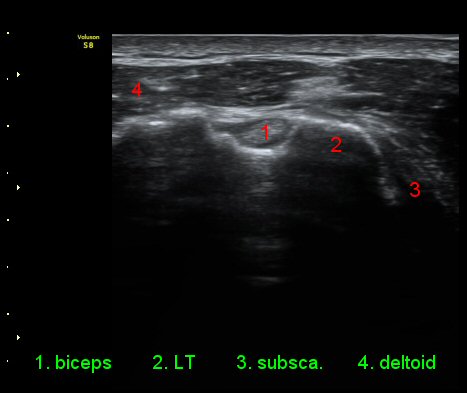

ÃÊÀ½ÆÄ °Ë»ç

ÀÌµÎ¹Ú±Ù°Ç È¾´Ü¸é°Ë»ç¿¡¼­ °ÇÁÖÀ§¿¡ ¼Ò·®ÀÇ ¼ö¾×Àú·ù¿Í Á¡¾×³¶³» ¾×Àú·ù°¡ °üÂûµÈ´Ù(»çÁø 1, 2).

ŽÃÊÀÚ¸¦ ¾à°£ ´Ù¸®ÂÊ, ³»ÃøÀ¸·Î À̵¿ÇÏ´Ï °ß°©ÇÏ±Ù°Ç Ç¥Ãþ¿¡ ¸¹Àº ¾çÀÇ ¼ö¾×Àú·ù°¡ °üÂûµÈ´Ù(»çÁø 3).